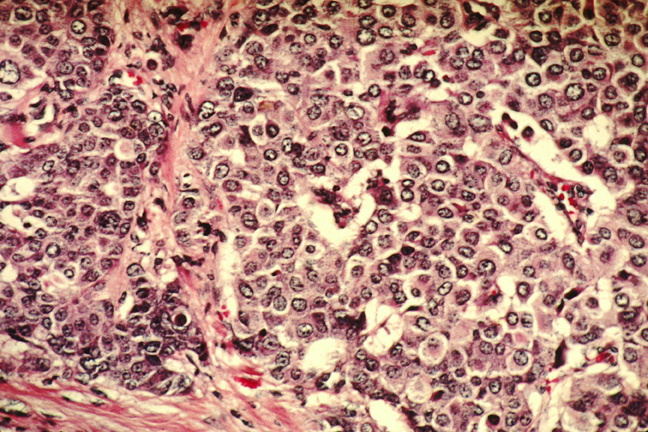

Ricercatori dell’Institut National de la santé et de la recherche médicale (INSERM), in collaborazione con l’Université Paul Sabatier e il Centre national de la recherche scientifique (CNRS), tutti in Francia, hanno fatto la scoperta rivoluzionaria che le cellule adipose, quelle che gli esperti chiamano adipociti, trovare una nicchia nei pressi dei tumori al seno.

Secondo il team, gli adipociti possono trasformare le caratteristiche delle cellule cancerose quando sono collegate ai tumori, quindi risultando in cellule cancerose più aggressive.

Il tessuto adiposo, per lo più composto da cellule adipose, rappresenta gran parte della parte esterna del seno. Le cellule adipose, conosciute per la loro capacità di immagazzinare e rilasciare i grassi, possono anche secernere molte proteine. Quindi, la questione chiave per i ricercatori era di determinare se tali proteine effettivamente contribuiscono allo sviluppo del cancro al seno.

Guidati da Philippe Valet dell’Institut des maladies métaboliques et cardiovasculaires (INSERM/Université Paul Sabatier) e da Catherine Muller dell’Institut de pharmacologie de biologie structurale (CNRS/Université Paul Sabatier), i ricercatori hanno usato un originale sistema di co-coltura di cellule tumorali mammarie e adipociti, che ha mostrato un cambiamento nella secrezione di alcune delle loro proteine, tra cui anche le proteine infiammatorie come l’interleuchina 6 (IL-6).

Il team ha scoperto che le cellule adipose interagiscono con il tumore, provocando un aumento del suo “potenziale di colonizzazione” e quindi della sua aggressività. I ricercatori hanno anche scoperto che gli adipociti situati nei pressi di grandi tumori umani, con invasione gangliare, contenevano più IL-6. La proteina potrebbe pertanto avere un ruolo nella diffusione del tumore al seno indotta dagli adipociti.